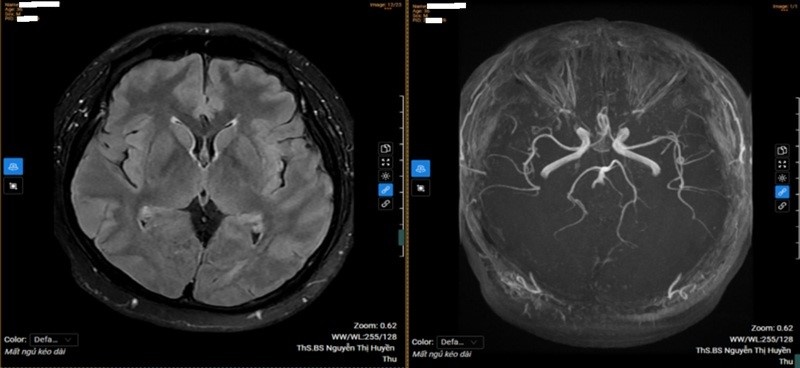

| Kết quả chụp MRI sọ não của bệnh nhân |

Các thăm dò chuyên sâu như cộng hưởng từ sọ não và điện não đồ không phát hiện tổn thương thực thể. Tuy nhiên, đo lưu huyết não cho thấy giảm lưu lượng máu ở một số hệ động mạch quan trọng, phản ánh ảnh hưởng của stress kéo dài lên tuần hoàn não. Từ tổng hợp lâm sàng và cận lâm sàng, bệnh nhân được chẩn đoán mất ngủ không thực tổn liên quan đến áp lực công việc.